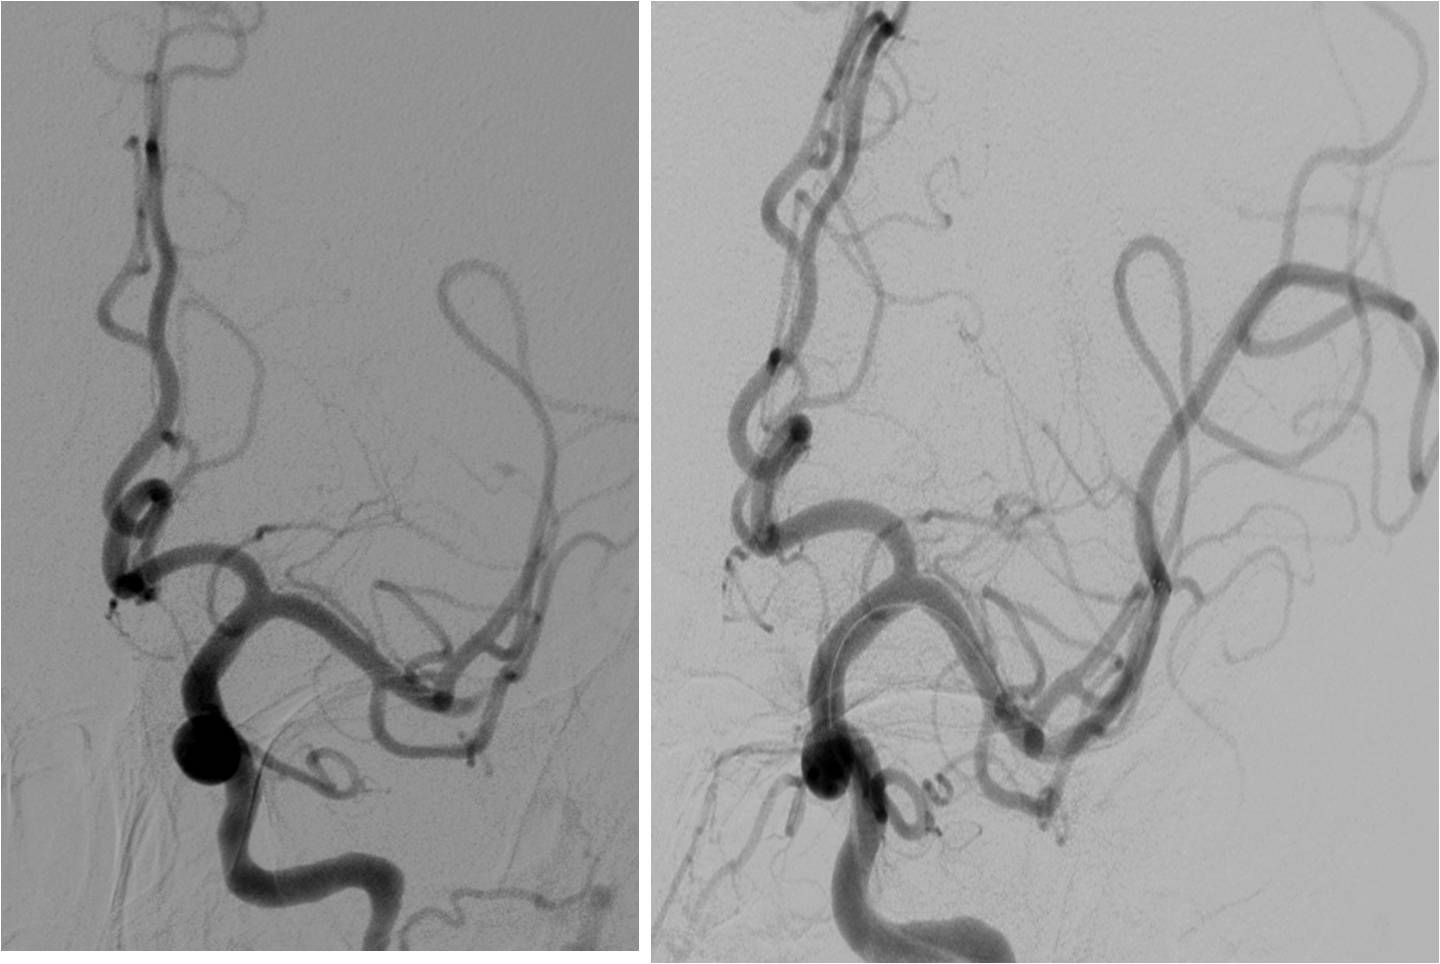

》男性,43岁,头痛、头晕伴发作性意识不清10余天入院。脑电图异常,查体无阳性体征。入院诊断“病毒性脑炎”。

》入院第3天,突发混合型失语伴右侧肢体活动不灵。

》头MRI+MRA:左侧岛叶斑片状异常信号,左侧颈内动脉不显影,左侧大脑中动脉显影较淡,远端分支较少。

》重点脑血管造影